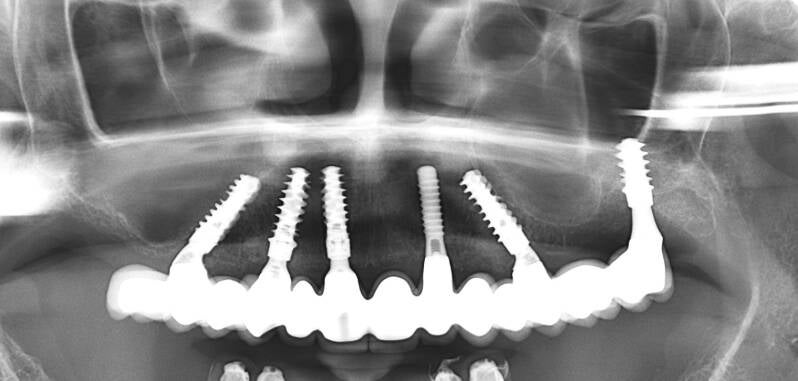

Rehabilitación de atrofias severas tanto maxilares como mandibulares mediante Implantes Cigomáticos e Implantes Personalizados Subperiósticos